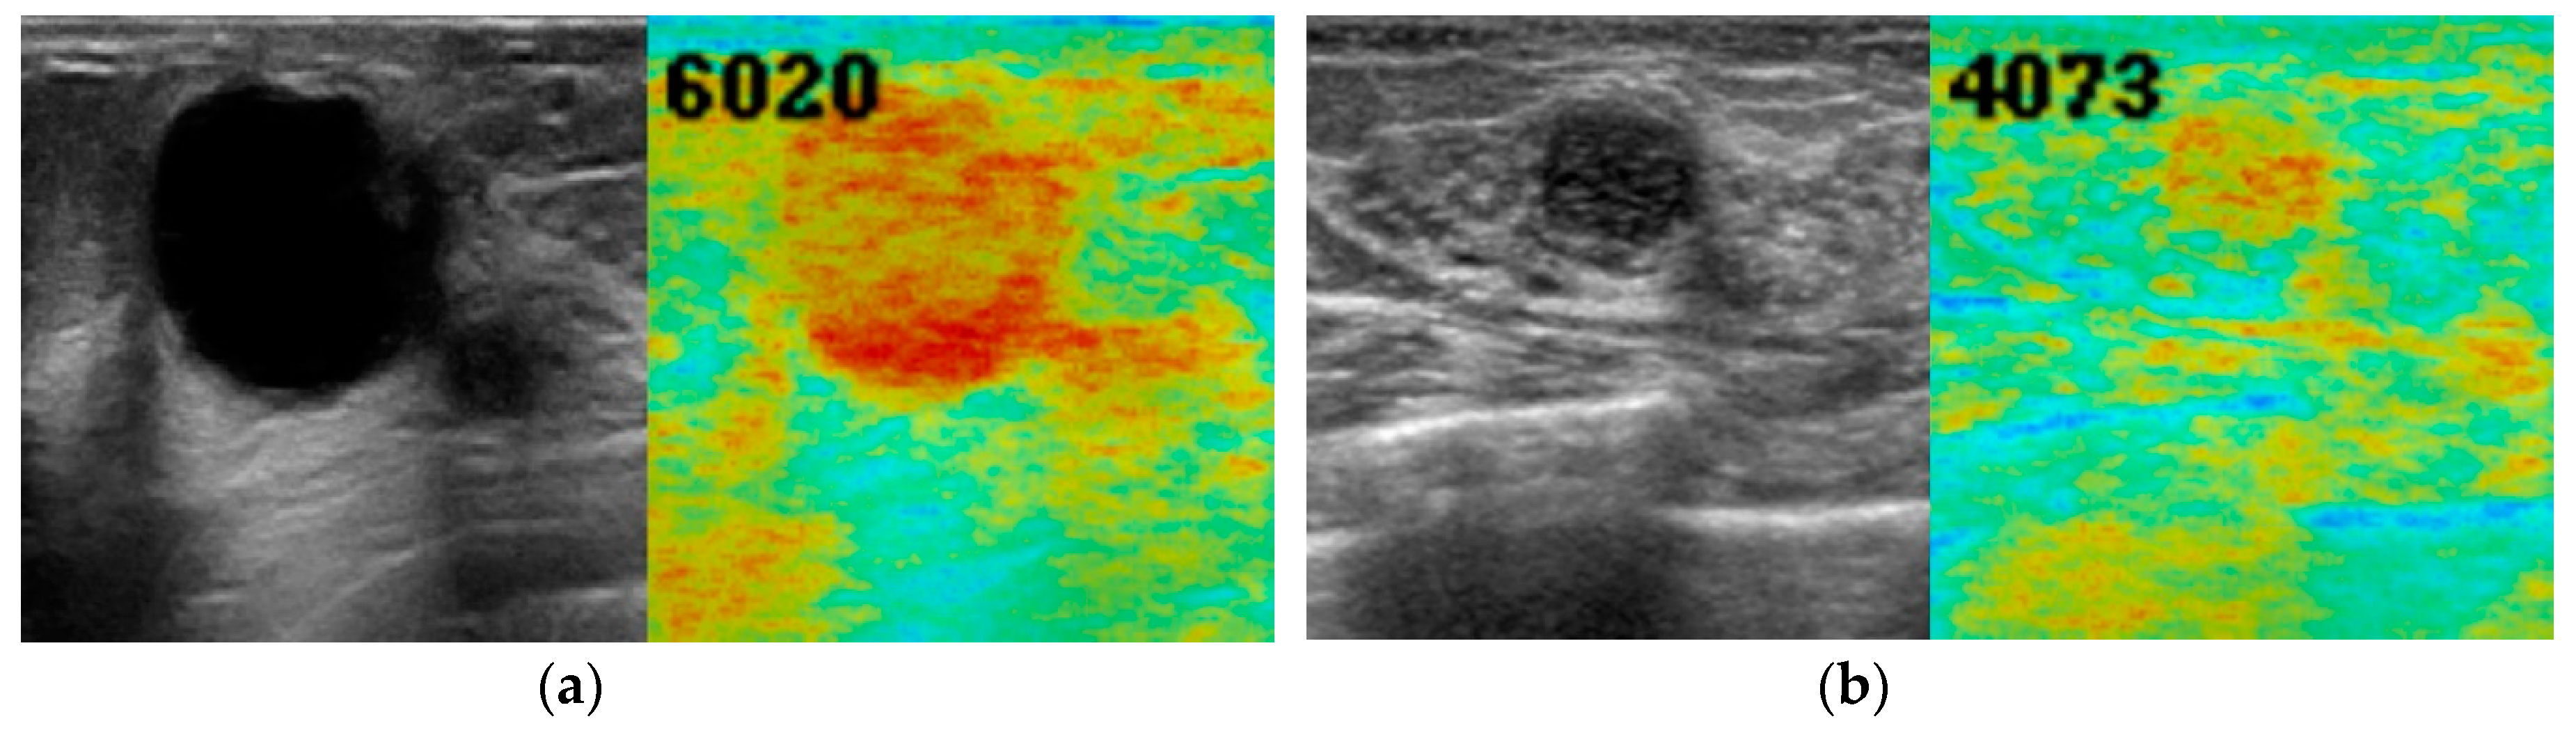

| Benign | 5283.4 ± 953.3 | 3411 | 8082 | ||

| Malignant | 6047.0 ± 842.1 | 4249 | 8170 | ||

| All | 5269.1 ± 1107.2 | 3136 | 8170 | ||